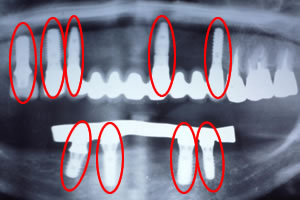

症例5![]() 処置前

![]() レントゲン写真